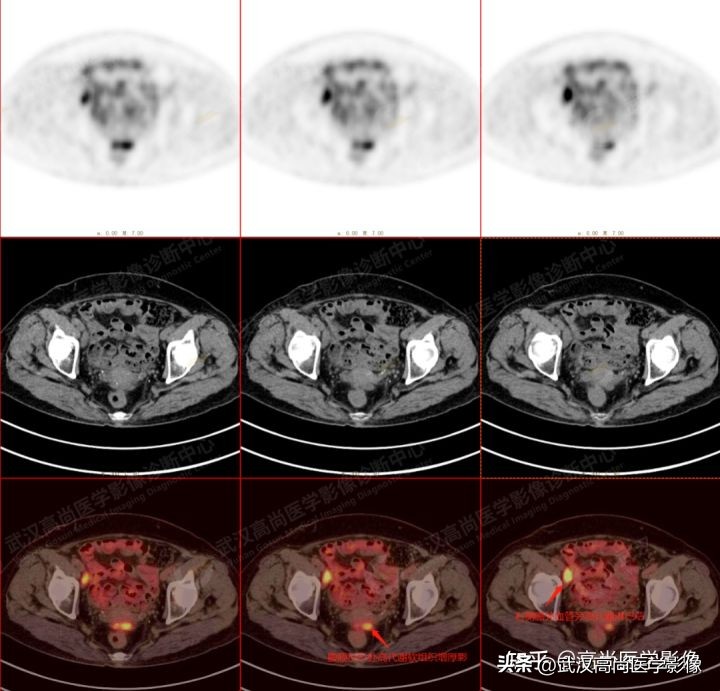

1. 右侧髂血管旁及腹股沟多发高代谢增大淋巴结,腹膜反折处高代谢病灶,均考虑为转移。

2. 右侧附件区囊性低密度灶,代谢减低,多考虑为良性病变(囊肿)。

2、 右侧附件囊性病变,体积小,密度均匀,边界较清楚,囊壁光滑均匀,代谢减低,无明显囊壁厚薄不均、壁结节、线性分隔、实性成分、边界不清及代谢增高等表现,亦无明显腹水征象,结合年龄及绝经史,综合考虑为良性病变(囊肿可能)。

3、 病史提供右侧腹股沟淋巴结细针穿刺结果为转移性癌(但检查时不知为浆液性癌),肿瘤指标CA199、AFP正常,而妇科相关肿瘤指标CA125未查。

4、 类似此例的女性患者(特别是老年人)若有转移灶但原发灶不明者,而附件区有囊性低密度灶,结合淋巴结转移病理为浆液性癌或CA125指标升高,附件区病灶无论大小及有无葡萄糖代谢增高,均需警惕浆液性癌可能,请结合临床。